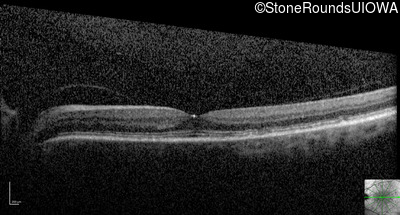

Visit at age: 58 years (Visit 2)

Optical Coherence Tomography - Right - 20/250

Exemplar / OCT Stack